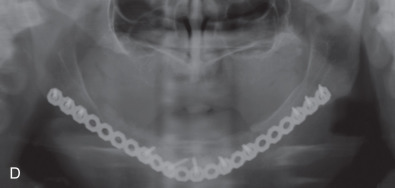

All of these systems allowed for convalescent function – life without MMF. RIF had the potential of dramatically shortening the course of treatment. However, its use was highly technique-sensitive with a steep learning curve. Thus, the incidence of complications increased dramatically due to operator error. Complications related to inadequate reduction – “the OIF” (open internal fixation … without the reduction) ( Figs. 1.16.1–1.16.3 ), inadequate fixation ( Figs. 1.16.4–1.16.7 ) and surgical misadventure ( Fig. 1.16.8 ) began to appear. Indeed, by the early 1990s operator error was the number one cause of mandibular fracture complications. Quite obviously, RIF is very unforgiving. When done poorly, one has a rigidly fixed mistake. The latest series of misadventures are related to the use of IMF screws. Bone-anchored arch bars will most likely be next. Not all believe that RIF and convalescent function is cost-effective with respect to the increased cost, potential for complications, and patient acceptance.